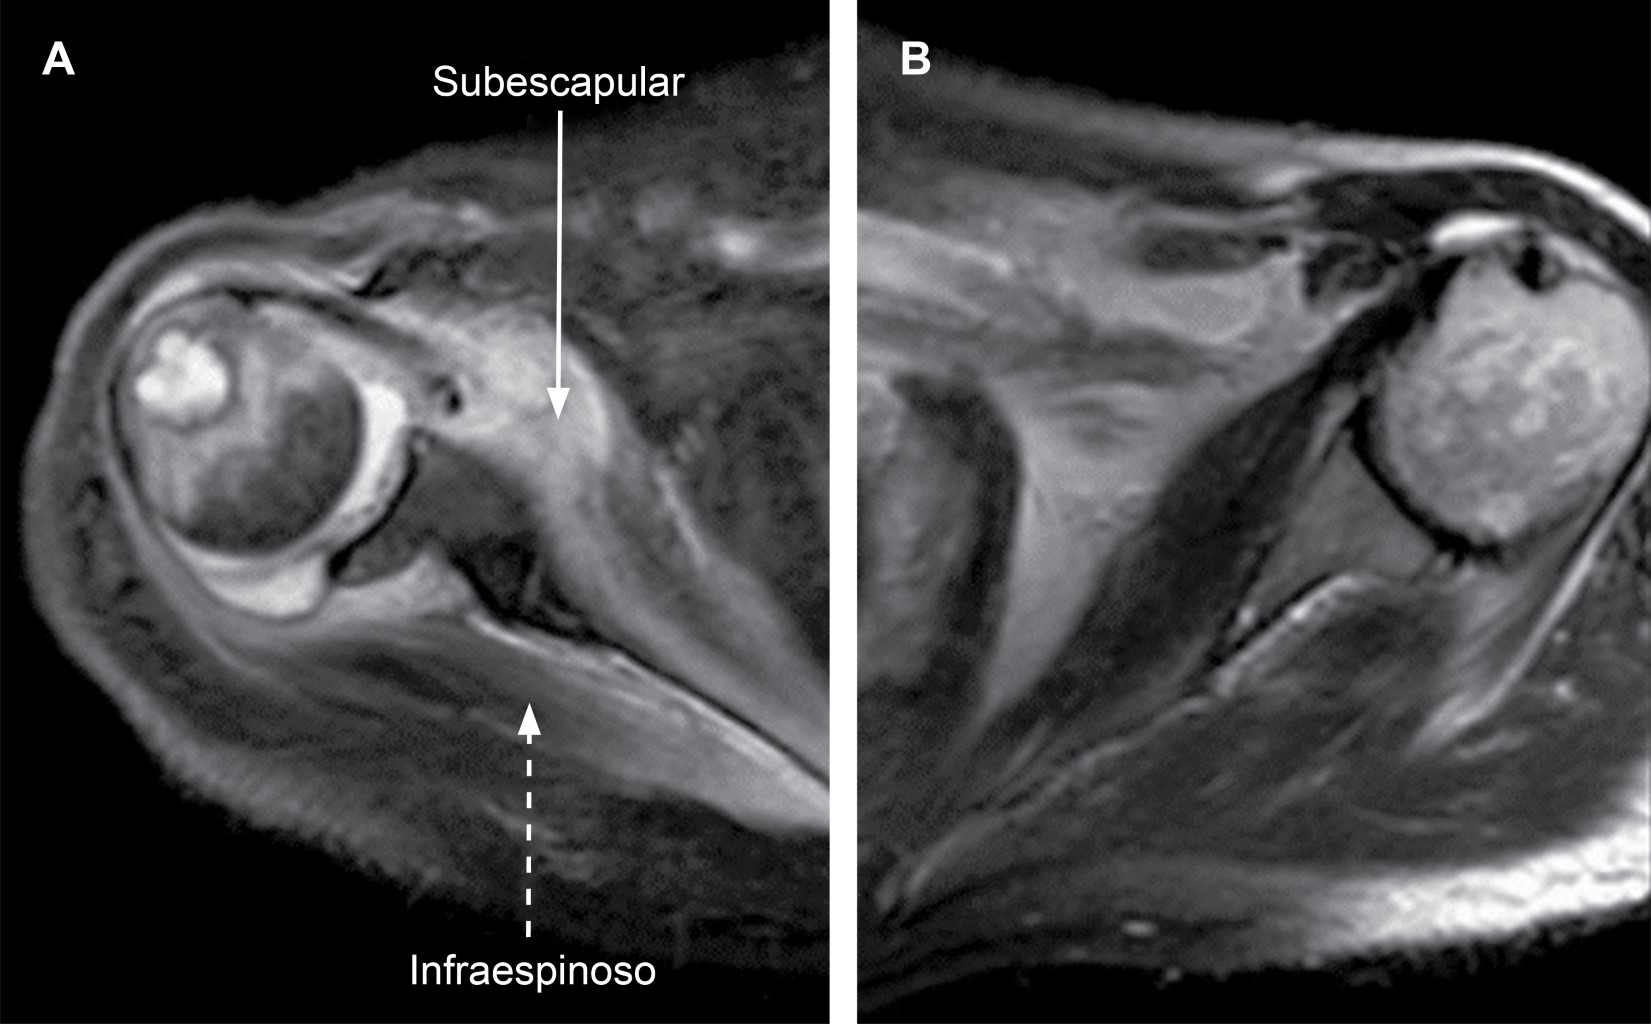

El síndrome de Parsonage-Turner1 (SPT) o plexitis braquial fue mencionada inicialmente por Feinberg en 1897 en un caso asociado con influenza, es una neuritis del tronco superior del plexo braquial; Parsonage y Turner2 la describieron en 1948 en 136 soldados y posteriormente en 82 pacientes; es bilateral en 25% de los casos, con incidencia de 1.5 casos/100,000, principalmente en varones entre la tercera y quinta década de la vida. Esta enfermedad es de etiología desconocida, se ha descrito asociación con factores desencadenantes (coexiste en ocasiones con procesos inmunes). De manera inicial se manifiesta con una fase de dolor agudo y súbito en hombro irradiado a la extremidad; posteriormente se presenta paresia que llega a parálisis (fase de parálisis y amiotrofia) del deltoides, supraespinoso, infraespinoso y/o serrato anterior; le sigue una etapa de recuperación que suele durar entre seis meses y un año, por lo general no deja secuelas en 75% de los casos. Es una enfermedad rara que debe ser parte del diagnóstico diferencial en cuadros de dolor en región proximal de miembros superiores cuando se asocian síntomas o signos neuromusculares. Se han descrito cuadros de amiotrofia neurálgica o del plexo braquial con carácter hereditario y transmisión autosómica dominante afectando al cromosoma 17 (17p25).3 La resonancia magnética es el estudio de elección, los datos observables son la aparición de señales hiperintensas en los músculos supraespinoso, infraespinoso y subescapular, que se interpretan como derivados del edema muscular secundario a la denervación (Figura 1).4 El tratamiento es sintomático con analgésicos, fisioterapia y rehabilitación.

Figura 1